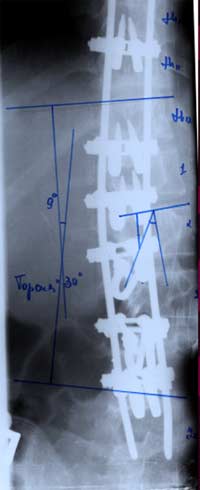

Нами проведен анализ 209 случаев

оперативного лечения сколиотической

деформации II - IV степени с использованием

двухпластинчатого эндокорректора с

многоуровневой фиксацией. Срок наблюдения

составил от 1 до 4-5 лет с наличием

корректора и от 1 до 3 лет после его

удаления. Средний возраст 13,8 года.

Врожденный сколиоз был только в 3,83%

случаев. Деформация с наименьшим углом

по Коббу составила 21°, с наибольшим

124°. Основное число прооперированных

больных было с углом искривления в

диапазоне 31°-70°. Среди них у 43% угол

искривления составил 51°- 60°.

У больных со II степенью деформации

коррекция составила 96,56 - 100%

|

При

сколиозе III степени - 88,19 - 91,26%.

сколиозе IV степени с углом деформации

в диапазоне от 51° до 70° коррекция

составила от 79,2 до 84,8%. С углом от 71° дог

80° - 73,3 - 86,5%. С искривлением от 81° до 122°

удалось достигнуть одномоментно

коррекции в пределах 72,7 - 73,8%.

Коррекция

ротационной деформации при II степени

сколиоза была 61,83%.

При III степени удалось добиться В среднем

коррекции на 59,2%, а при IV степени только

на 34,04%. Более низкий процент коррекции

сколиотической деформации, как боковой,

так и ротационной, объясняется тем, что

как правило оперативному лечению с IV

степенью подвергаются пациенты с

запущенными стадиями заболевания, как

правило с законченным ростом, более

взрослые, с достаточно уже жестким

фиксированным позвоночником. И не менее

важно то, что угол деформации большой,

часто более 80° - 90°, а это при одномоментной

коррекции чревато неврологическими

осложнениями различной степени тяжести.